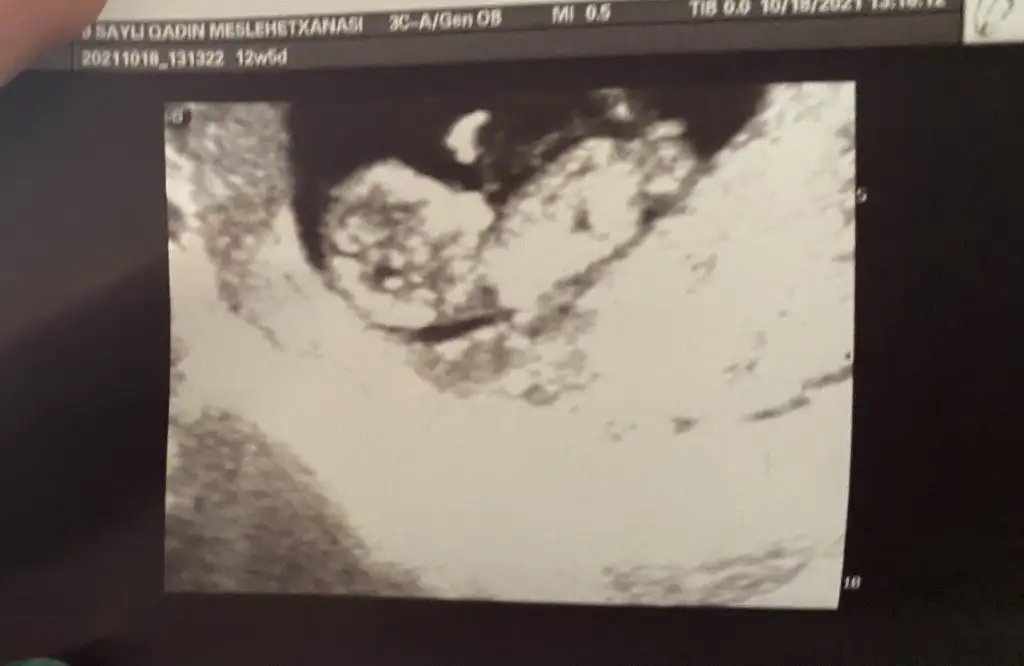

ıkra meyraMerhaba ben bu siteyi yeni keşfettim hamileyim çok şükür benim bebiş 12 haftalık cinsiyetini merak ediyorum doktor birsey demedi. Bana kız gibi geldi ama bilemedim Size foto gönderiyirum tahmin eder misiniz

Kız görünüyorMerhaba ben bu siteyi yeni keşfettim hamileyim çok şükür benim bebiş 12 haftalık cinsiyetini merak ediyorum doktor birsey demedi. Bana kız gibi geldi ama bilemedim Size foto gönderiyirum tahmin eder misiniz

Emin olmadım sanki erkek gibiIkra meyra Merhaba, bu ultrason goruntuleri son adet tarihine gore 11+5, ultrason olcumune gore 12+3. Acaba cinsiyet icin bi yorum da bulunabilir misiniz ? Simdiden tesekkur ederim.

Doktor %70 kiz gibi ama daha erken onumuzdeki ay net belli olur dedi. Fakat prof dr oldugu icin yanilacagini sanmiyorum. Senin dr baya namini duydum sitede. Sen de emin olamamissin o zaman kız mi geliyor acabaEmin olmadım sanki erkek gibi

BakalımDoktor %70 kiz gibi ama daha erken onumuzdeki ay net belli olur dedi. Fakat prof dr oldugu icin yanilacagini sanmiyorum. Senin dr baya namini duydum sitede. Sen de emin olamamissin o zaman kız mi geliyor acaba